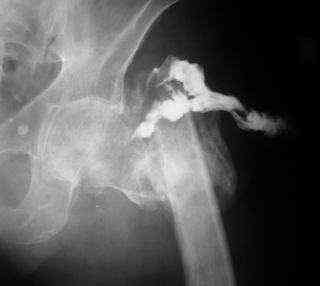

Если снимок справа по хронологии последний, то в тазобедренном сустава наступил анкилоз. Это хороший плюс костной ткани для постановки чашки эндопротеза, но отсутствие сохранения биомеханической оси бедренной кости ставит под вопрос благоприятный вариант усановки ножки эндопротеза.... Учитывая выполненную остеотомию, не считаю выполнение скелетного вытяжения лишенным смысла, для восстановления оси конечности с последующим, возможно, индивидуальным эндопротезированием.

Очень признателен Вам за ответ, но позвольте мне не согласиться с Вами. Я бы пока не делал вывод о анкилозировании тазобедренного сустава. На рентгеновских снимках, да и по данным компьютерной томографии (а этот метод один из самых современных и информативных), хорошо прослеживается постоянной ширины щель между головкой бедренной кости и вертлужной впадины. Кроме того, несложно увидеть разницу "шеечно-диафизарного угла" до и после выполнения тракции в аппарате. Хотя, Алексей, даже если я и прав, это не сильно облегчает нашу задачу.